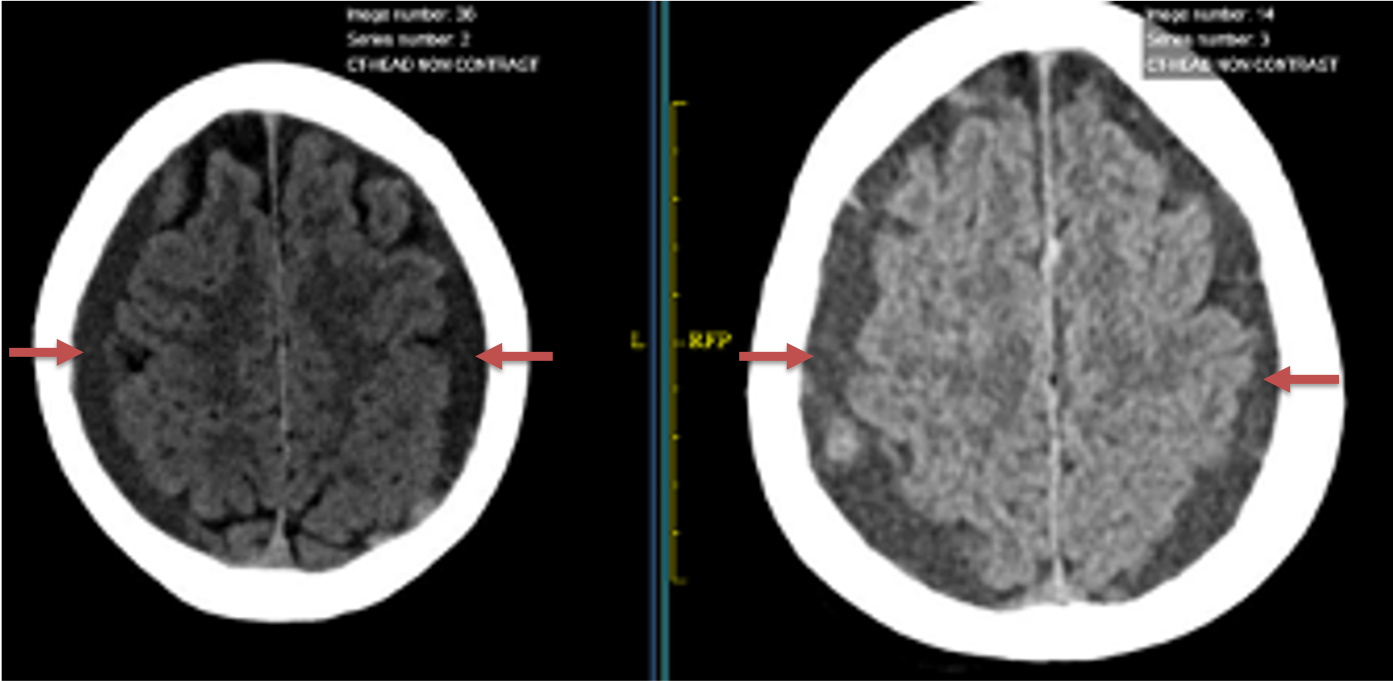

Clinically, the patient improved over the few weeks with the occasional transient twinge of a headache, but resolution of dizziness. Follow-up CT at 10 weeks demonstrated complete resolution of the bilateral subdural hematomas with our patient complete symptomatic and back to all of his activities of daily living. Considering his history of thrombocytopenia and CLL, we will continue to monitor him into the future and are excited about his progress and recovery. (Figure 4. A and B)

Figure 4. A and B) – 10 weeks following embolization demonstrates complete resolution of bilateral collections both acute and chronic.